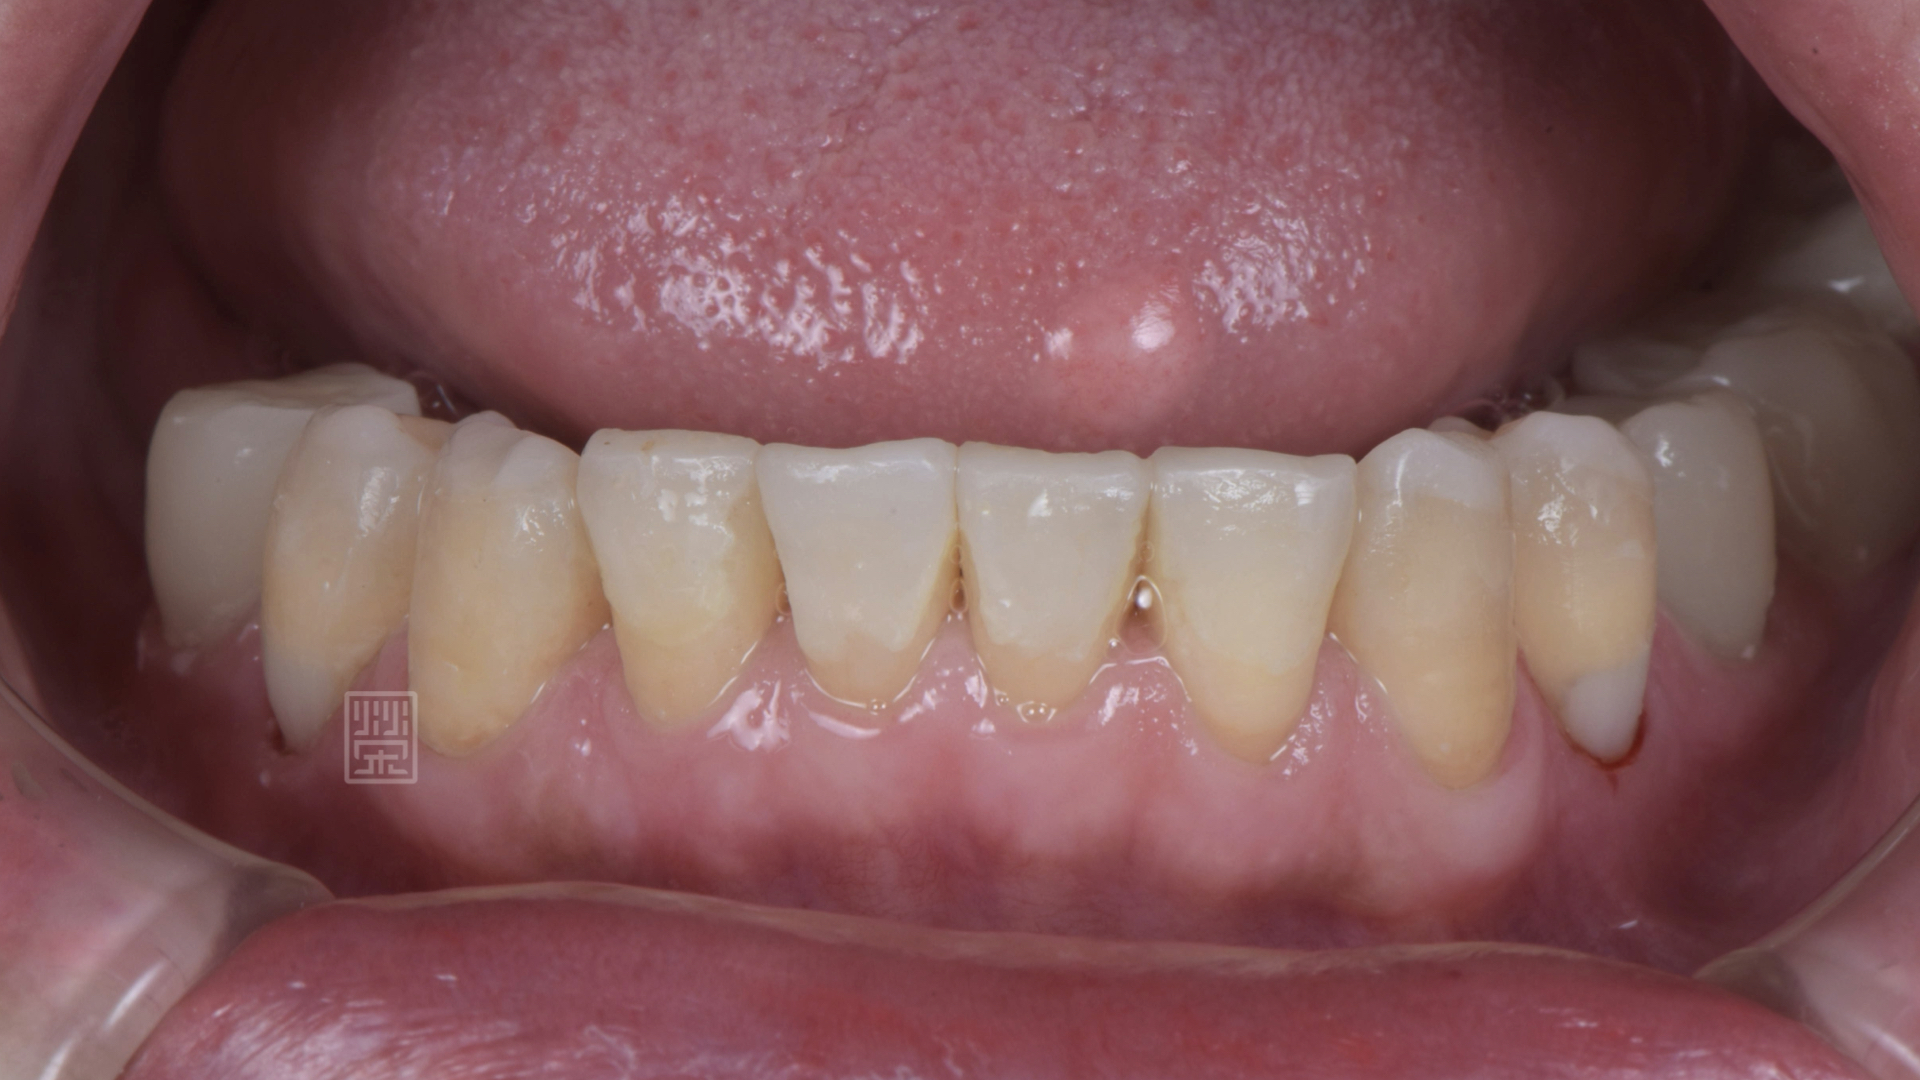

口內照片顯示,假牙黏膠未脫落、邊緣不秘貼,無法正常咀嚼及說話

更換臨時假牙後,恢復外觀與功能